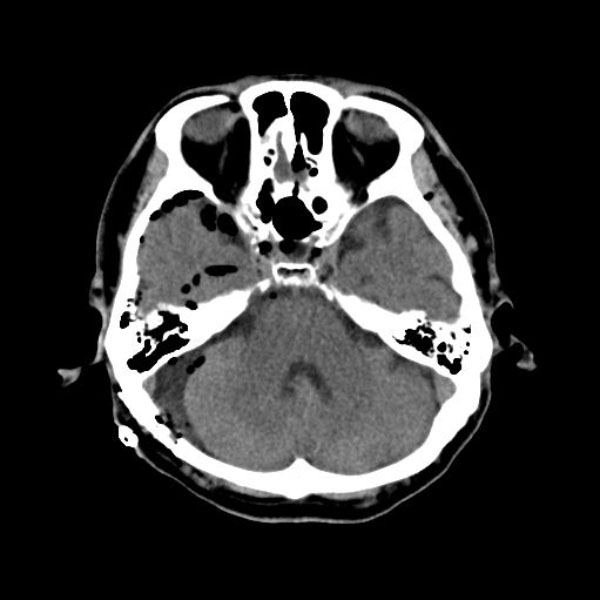

578

'26年2月

60代

右三叉神経痛

手術前